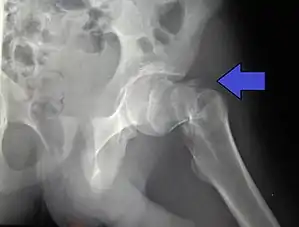

Uma fratura da anca (português europeu) ou do quadril (português brasileiro) é uma fratura óssea que ocorre na parte superior do fémur.[2] Os sintomas mais comuns são dor na região da anca, que se agravam com o movimento, e encurtamento de uma das pernas.[2] Geralmente a pessoa é incapaz de caminhar.[3]

A causa mais comum são quedas.[3] Entre os fatores de risco estão a osteoporose, o consumo de uma grande quantidade de medicamentos, o consumo de álcool e cancro metastático.[2][1] O diagnóstico é geralmente confirmado com radiografia.[2] Em alguns casos pode ser complementado com ressonância magnética, TAC, cintigrafia óssea.[3][2]